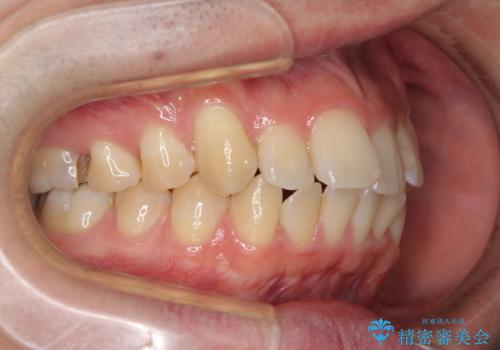

- 上下前歯のデコボコを気にして来院された患者様です。

口元はやや突出感がありましたが抜歯矯正をするほどではないため、舌突出癖を改善するトレーニングをしっかりと行っていただき、現在よりも唇が閉じやすい位置に仕上げていくこととしました。

下顎前歯が思っていた以上に動きが悪く、想定よりも期間がかかってしまいました。